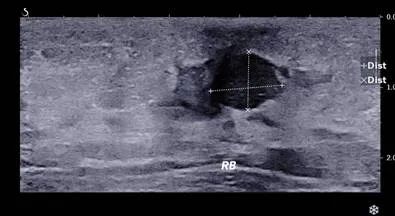

男性,38岁,来院行甲状腺B超检查,超声所见如图

解读:该男性甲状腺B超超声所见结节形态欠规则、纵横比失调,内回声不均,可见多发细点强回声,可见稀疏点状血流信号。恶性结节可能性大,需进一步检查。